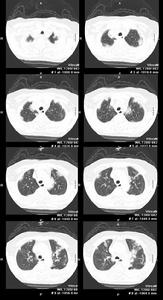

肺念珠菌病2、影像學檢查:兩肺紋理增深或呈瀰漫性小片狀或斑點狀陰影部分可融合成大片緻密影邊緣模糊形態,多變發展迅速病變大多位於中下肺野部分,病例伴胸膜改變慢性病變呈纖維條索狀陰影和代償性肺氣腫。

3、X線檢查:顯示兩肺紋理增多,或呈瀰漫性小片狀或斑點狀陰影,部分可融合成大片緻密影,邊緣模糊,形態多變,發展迅速。病變大多位於中下肺野,肺尖較少受累。